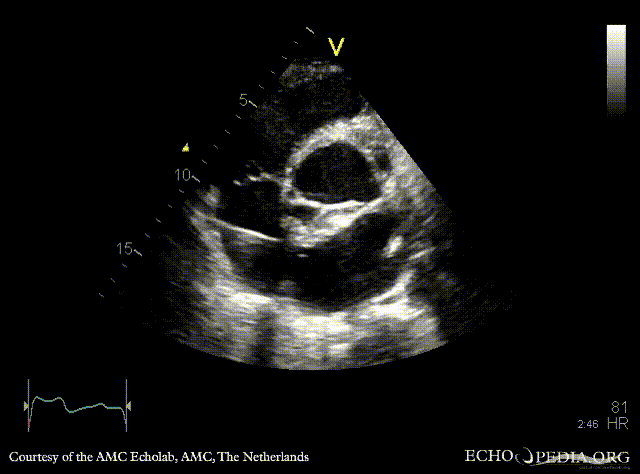

Abscess of aortic valve prosthesis

Courtesy of: AMC Echolab, AMC, The Netherlands

PSAX: abscess of aortic valve prosthesis A4CH with Color Doppler: flow from abscess into the left atrium, severe mitral regurgitation